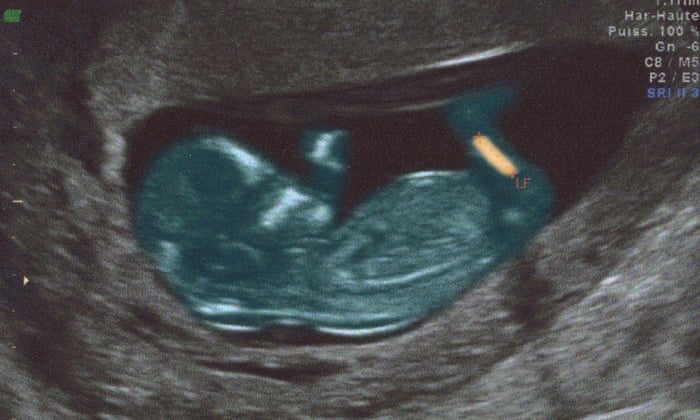

You may be able to hear – and see – your baby's heart beat for the first time when you're about 8 weeks pregnant if you have an early ultrasound exam. 7 weeks & 2 days Ultrasound & we hear the heartbeat!. 7 weeks pregnant with twins already.

Finding a baby’s heartbeat takes a lot of practice and if you can’t find it, it’s not usually a sign of a problem, just that baby has moved away from the monitor. I am six and a half weeks pregnant and had my first ultrasound and am now very worried. Using a transvaginal ultrasound, a developing baby's heartbeat should be clearly visible by the time a woman is seven weeks pregnant.

But a transvaginal ultrasound is able to find the baby's heartbeat quite early between 6 to 7 weeks. However, it isn’t uncommon to be unable to detect a heartbeat via ultrasound until closer to 7 or 8 weeks. Find out more about week 6 of pregnancy in our informative pregnancy week by week series.

Sometime between 6 weeks and 9 weeks of pregnancy, your practitioner (and/or a trained sonographer) will perform your first-trimester ultrasound. Hi ladies, I just wanted to find out if the doc will be able to see or hear the heartbeat at 7 + 2 via abdominal ultrasound?. What does it mean if the yolk sac was visible but no baby, heartbeat, or fetal pole was seen on my 7 week ultrasound?.